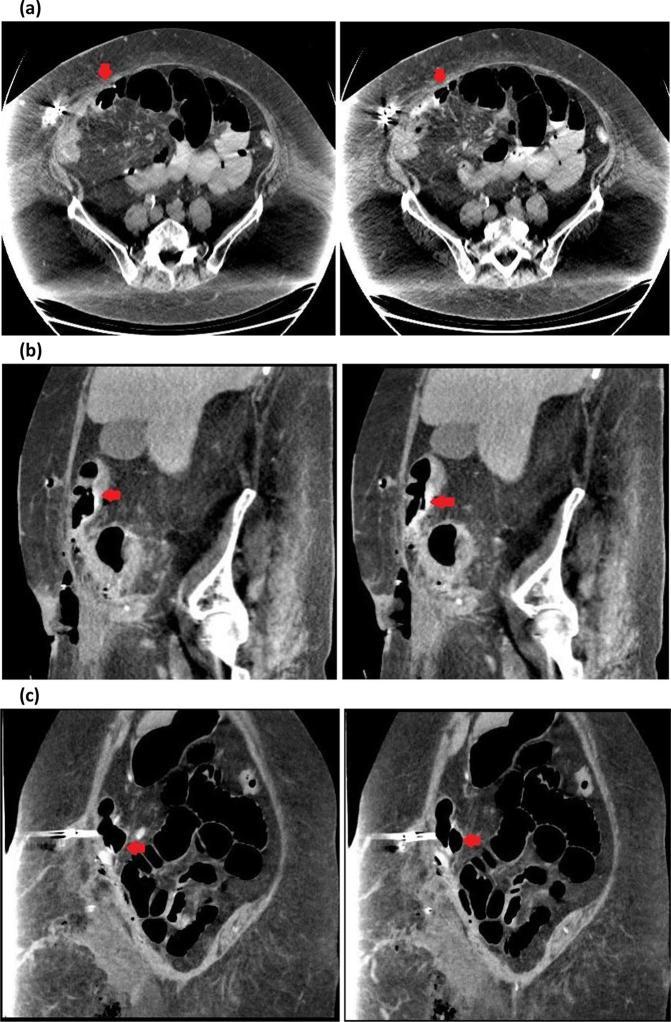

Laparoscopic-adjustable gastric band (LAGB) complications are increasingly recognised as follow-up time increases. These are most commonly related to the gastric band or port site, but complications of the connecting tubing are also reported. We present a case of LAGB tubing penetration through the transverse colon causing abdominal sepsis in a complex surgical abdomen and review prior published cases of abdominal viscus penetration by LAGB tubing. Like complications involving all LAGB components, these often present with non-specific abdominal signs and symptoms and undergo abdominal CT as an early investigation. This makes knowledge of normal and pathological imaging features of LAGB components important in radiology practice.

随着随访时间的增加,腹腔镜可调节胃束带(LAGB)并发症越来越受到关注。这些并发症最常见于胃束带或端口部位,但也有连接管并发症的报道。我们报告一例LAGB连接管穿透横结肠导致复杂手术腹部腹腔感染的病例,并回顾既往发表的LAGB连接管穿透腹腔脏器的病例。与所有LAGB组件相关的并发症一样,这些并发症通常表现为非特异性腹部体征和症状,早期检查会进行腹部CT。这使得了解LAGB组件的正常和病理影像特征在放射学实践中很重要。